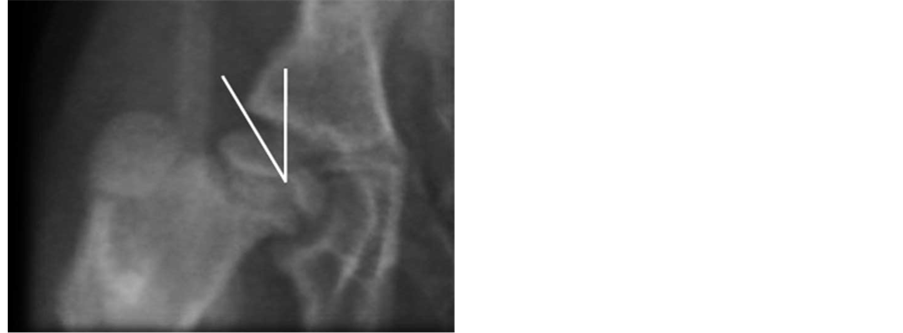

Figure 5. Acetabular depth index (ADI). Acetabulum Deepness is measured by drawing two vectors: the first one from the inferior- external edge until the superior-external of the acetabulum; the second is drawn a vector that is perpendicular to the anterior and that goes until the acetabular background marked by the line (ileopecten) of the iliop- ectineal eminence. It is calculated: p = (b/a) × 100% (n: 60%).

Orthopaedic Surgeon, Hospital Nacional de Pediatría J.P. Garrahan, Buenos Aires, Argentina